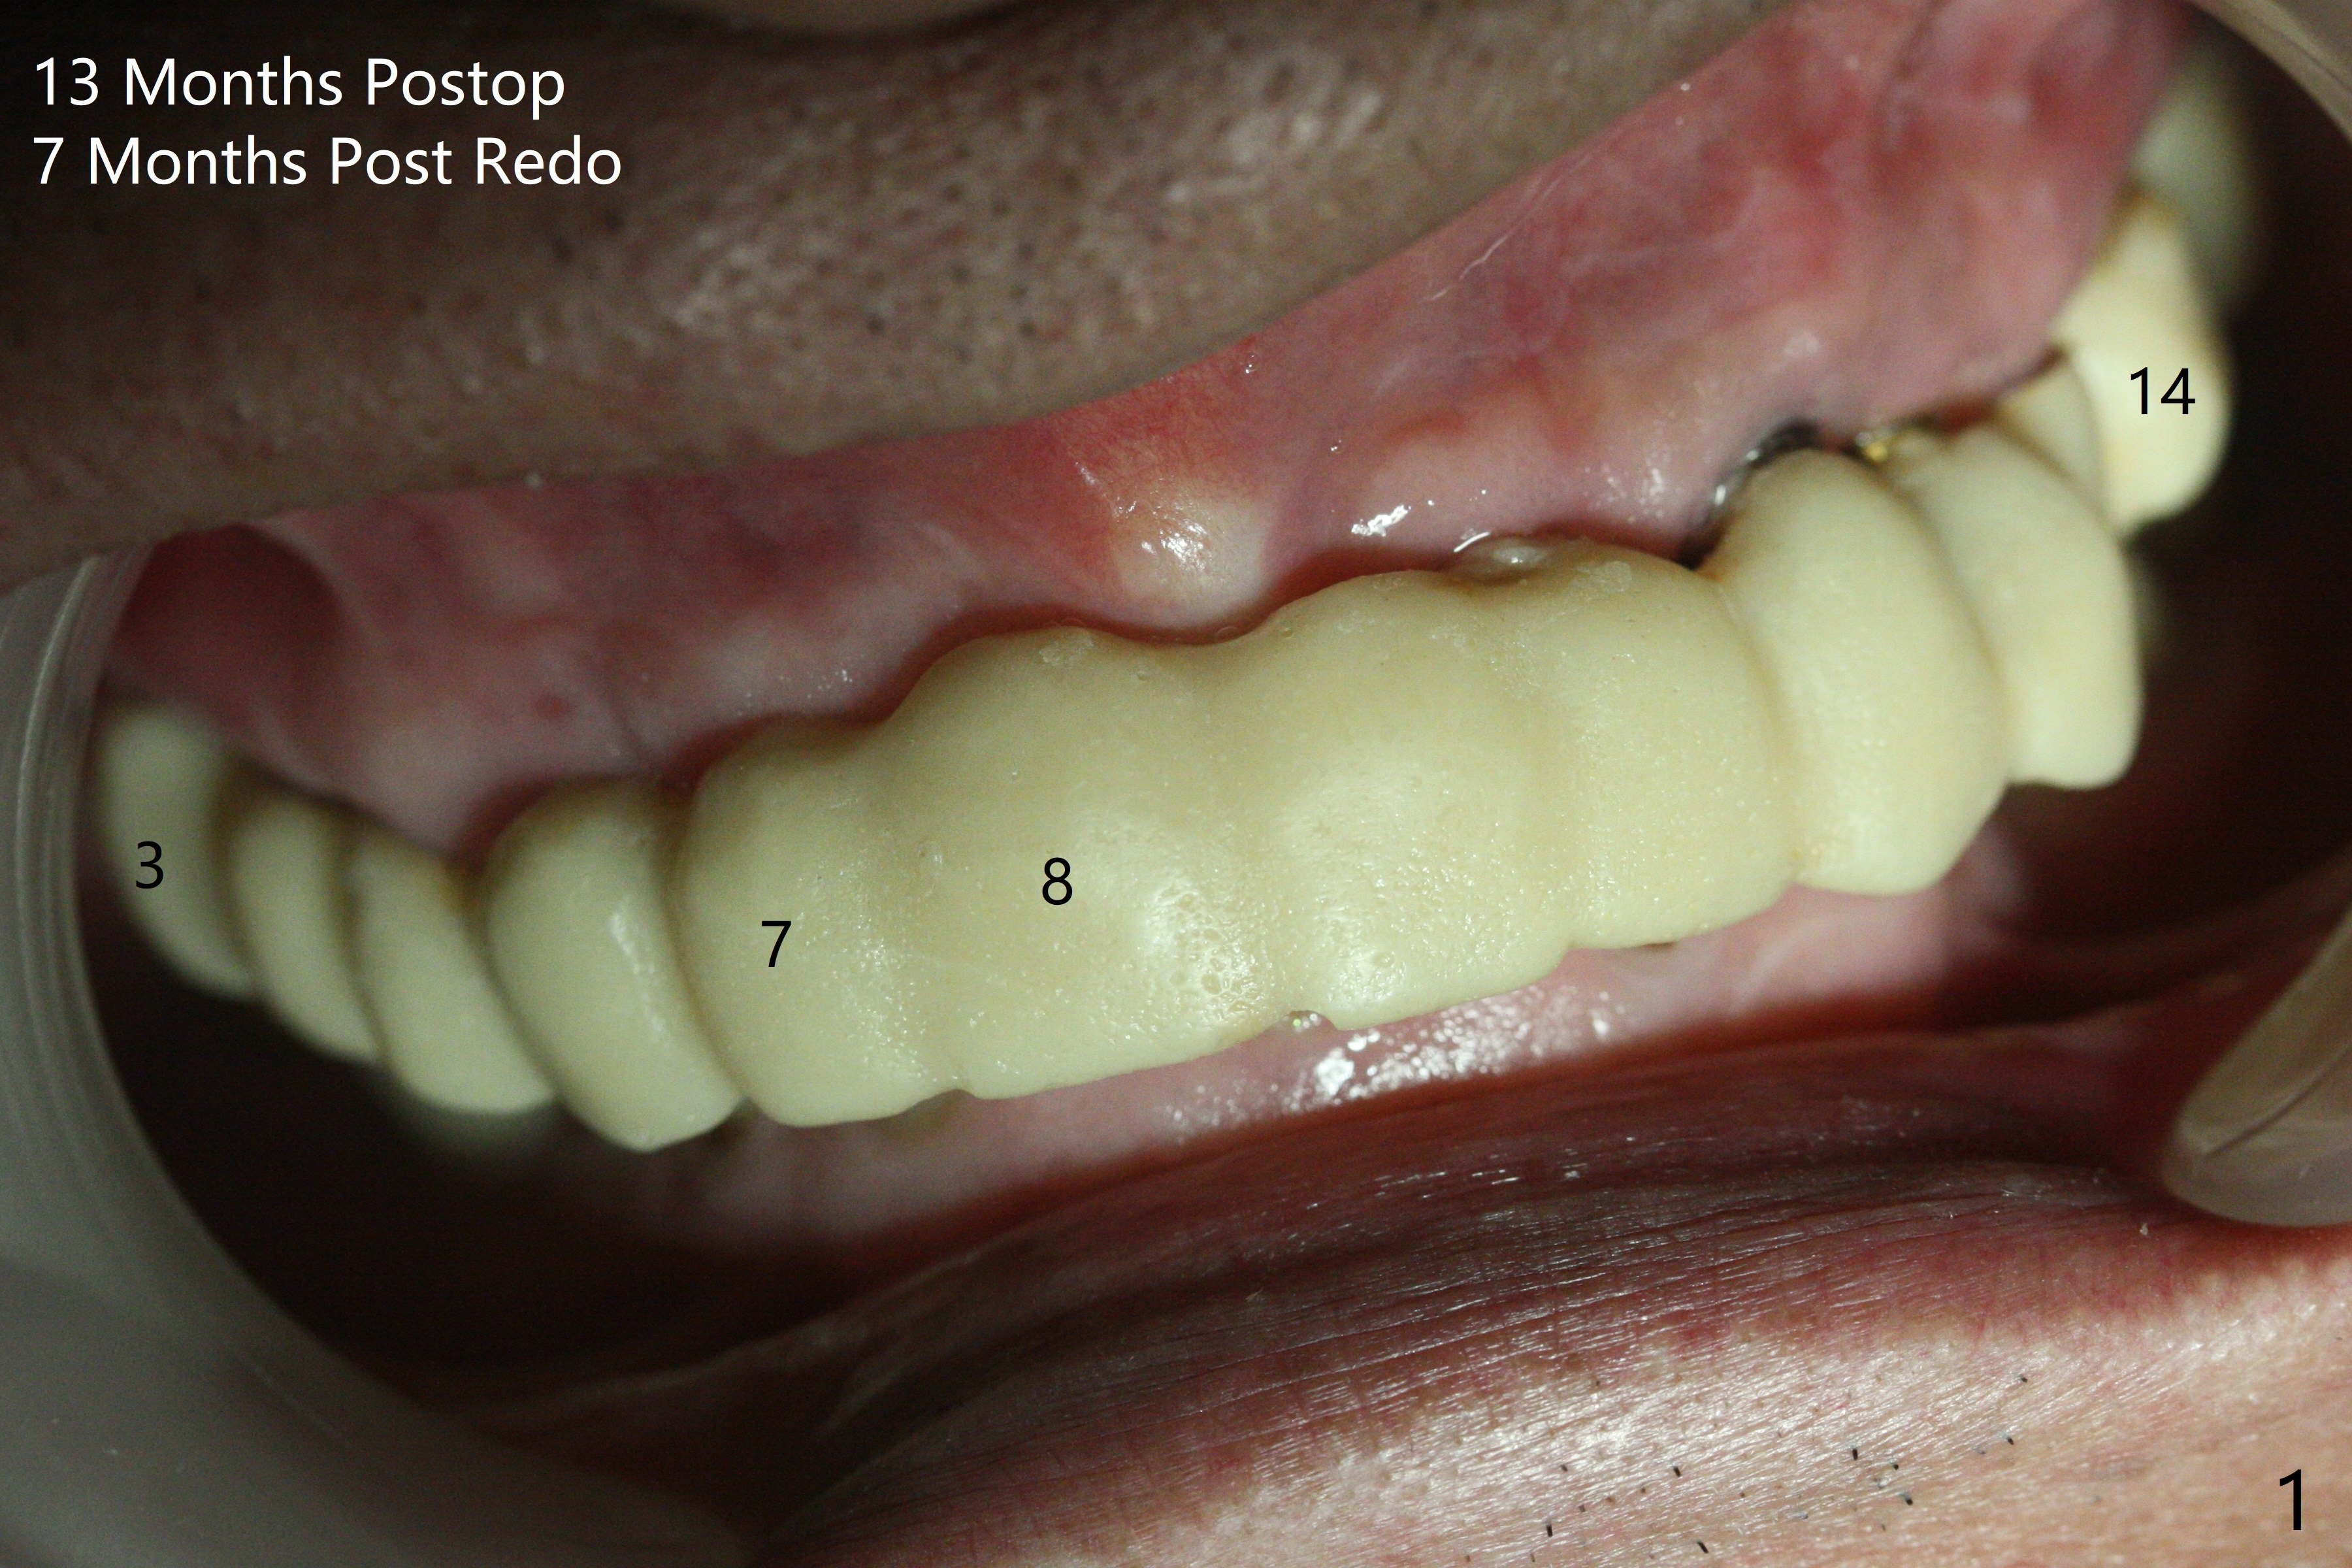

With temporarization of #3,4,13-15 (Fig.1), the anterior clearance is maintained (Fig.2). When provisional is removed, there is no papilla between #7 and 8 (Fig.3,4). After confirmation of complete seating of the abutments at #6 and 10 (Fig.5,6), gingivectomy is conducted with Diode laser (Fig.7,8). Following provisional being relined and modified, the anterior papillae form (Fig.9).